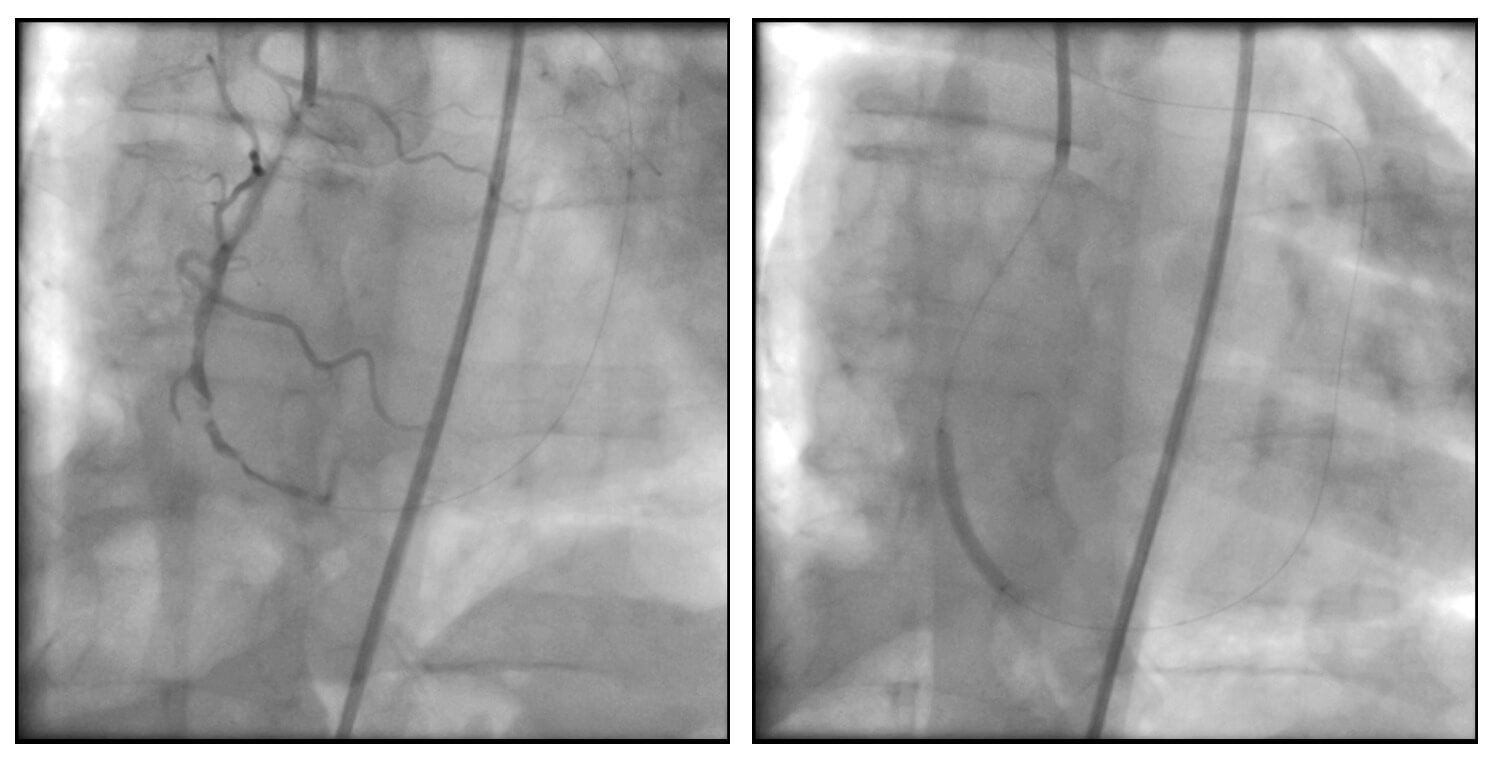

Coronariografía

- Dominancia derecha.

- Arteria descendente anterior izquierda: oclusión total crónica en el segmento proximal, con cap proximal ambiguo. J-CTO Score: 2 puntos.

- Recibe circulación colateral heterocoronaria desde las ramas septales inferiores.

Durante la externalización, el paciente presentó inestabilidad hemodinámica, evidenciándose una disección coronaria en la arteria coronaria derecha. Se procedió a la implantación de un stent, con mejoría clínica inmediata, lo que permitió continuar con el procedimiento planificado.

Posteriormente, se logró la predilatación de la oclusión con balones de bajo perfil y se implantó un stent DEStiny en el sitio de la lesión. Tras la apertura de la arteria, se identificó una lesión en la zona de reentrada (sitio de aterrizaje de la guía retrógrada desde la arteria coronaria derecha), por lo que se avanzó una guía por vía anterógrada y se implantó un segundo stent.